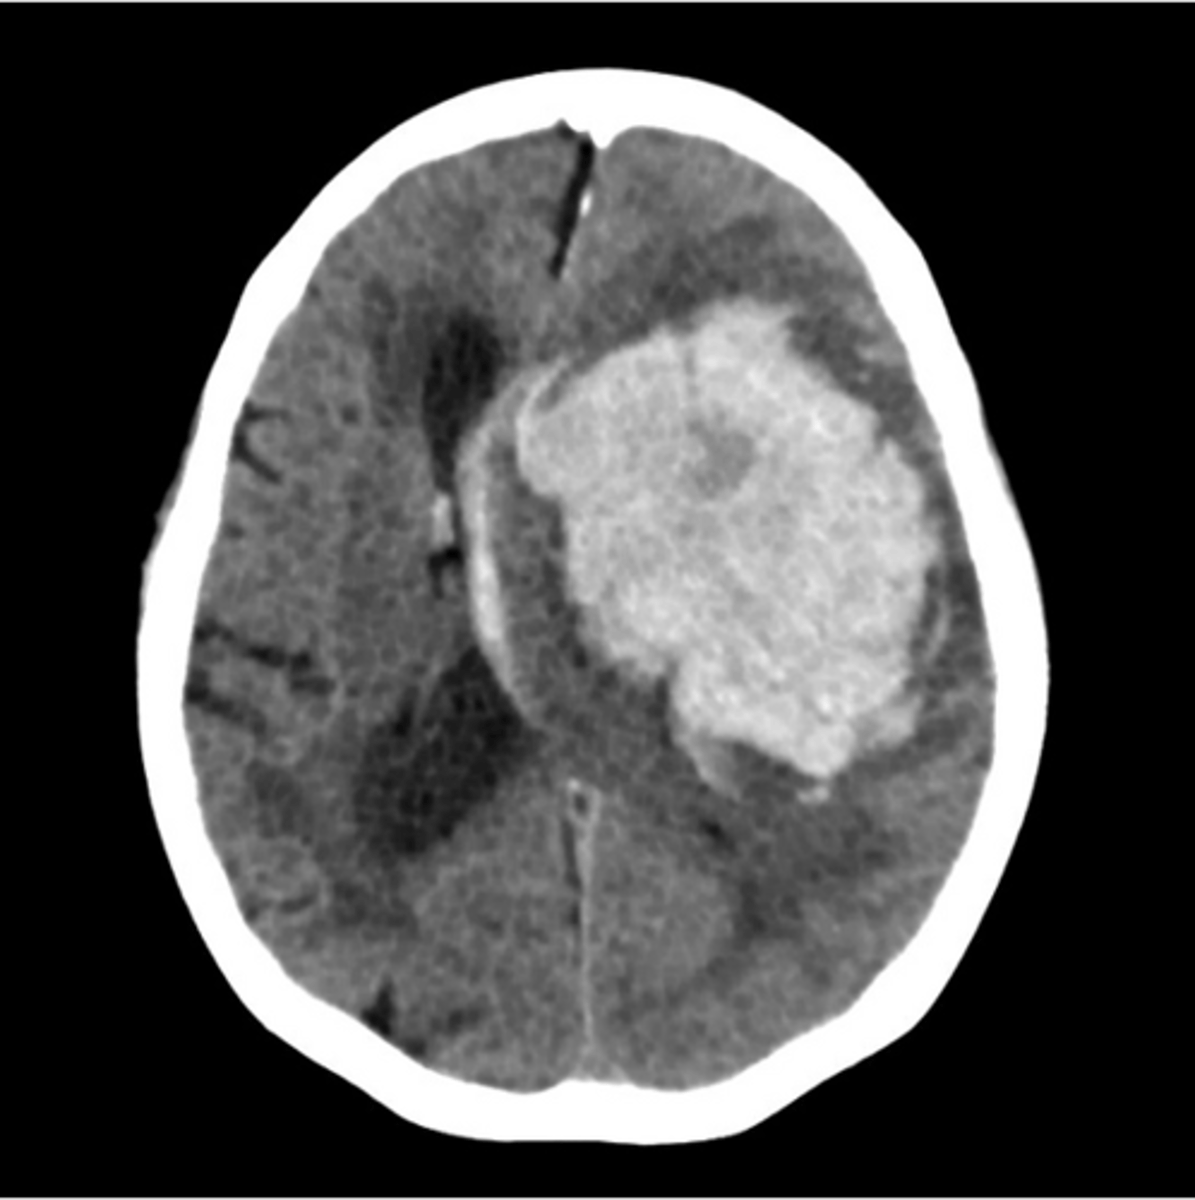

intracerebral hemorrhage

typically not trauma related; can often come from a ruptured AVM from uncontrolled HTN

Dark (on CT) means

White means